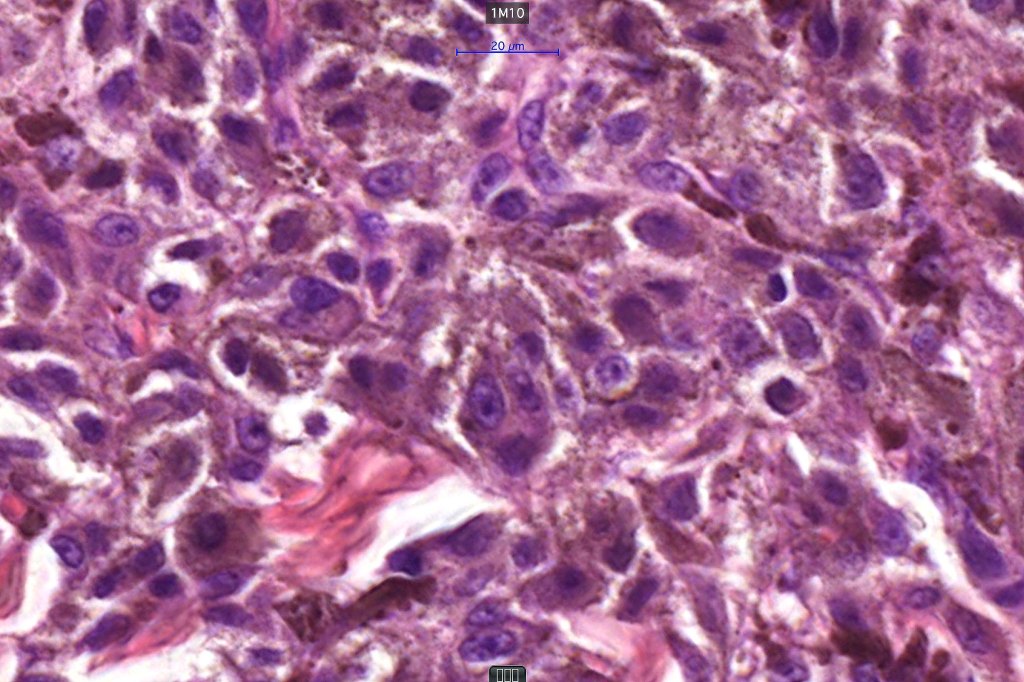

3. a deep penetrating nevus like lesion showing obvious signs of malignancy including greater pleomorphism than is usually seen combined with excessive mitotic activity, deep mitoses and atypical forms

4. melanoma which shows a deep penetrating architecture although the cytology remains epithelioid throughout